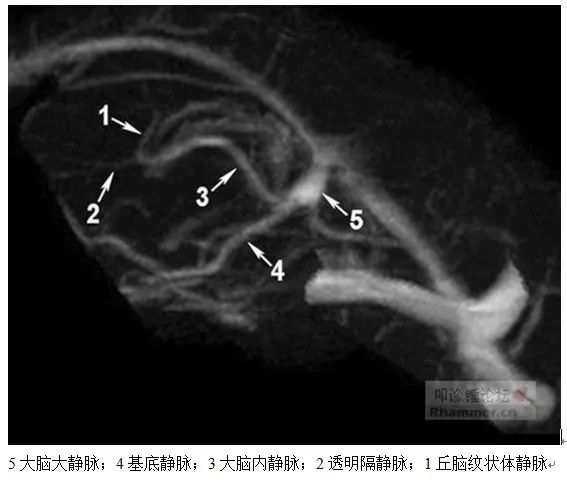

2. 大脑深静脉:主要收集侧脑室周围髓质、基底核、内囊、间脑及脑室脉络丛等深处的静脉血。分为大脑内静脉系和基底静脉系,两部分汇入大脑大静脉,注入直窦。

2.1 大脑大静脉:即Galen静脉,大脑深静脉的主干,由双侧大脑内静脉汇合形成,继而又接收双侧基底静脉血后,向上绕胼胝体压部以锐角注入直窦前端。同时还接收枕静脉、大脑后静脉等属支静脉血。

2.2 大脑内静脉:左右各一,汇成一条大脑大静脉,位于三脑室顶上方,主要由丘脑纹状体静脉、透明隔静脉和脉络膜静脉在室间孔处汇合而成。

丘脑纹状体静脉与透明隔静脉汇合为大脑内静脉向内下后方转向的夹角称为静脉角。该位置较固定,标志为室间孔位置所在。

2.3 基底静脉:即Rosenthal静脉,左右各一,在前穿质处由大脑前静脉、大脑中深静脉合成,并接收丘脑纹状体下静脉属支等静脉血。由前穿质附近起始,向后内经脚间窝外侧,在环池内绕大脑脚向后上方走行,穿过内外膝状体之间汇入大脑大静脉。左右基底静脉间存在交通静脉(前交通静脉、后交通静脉)。